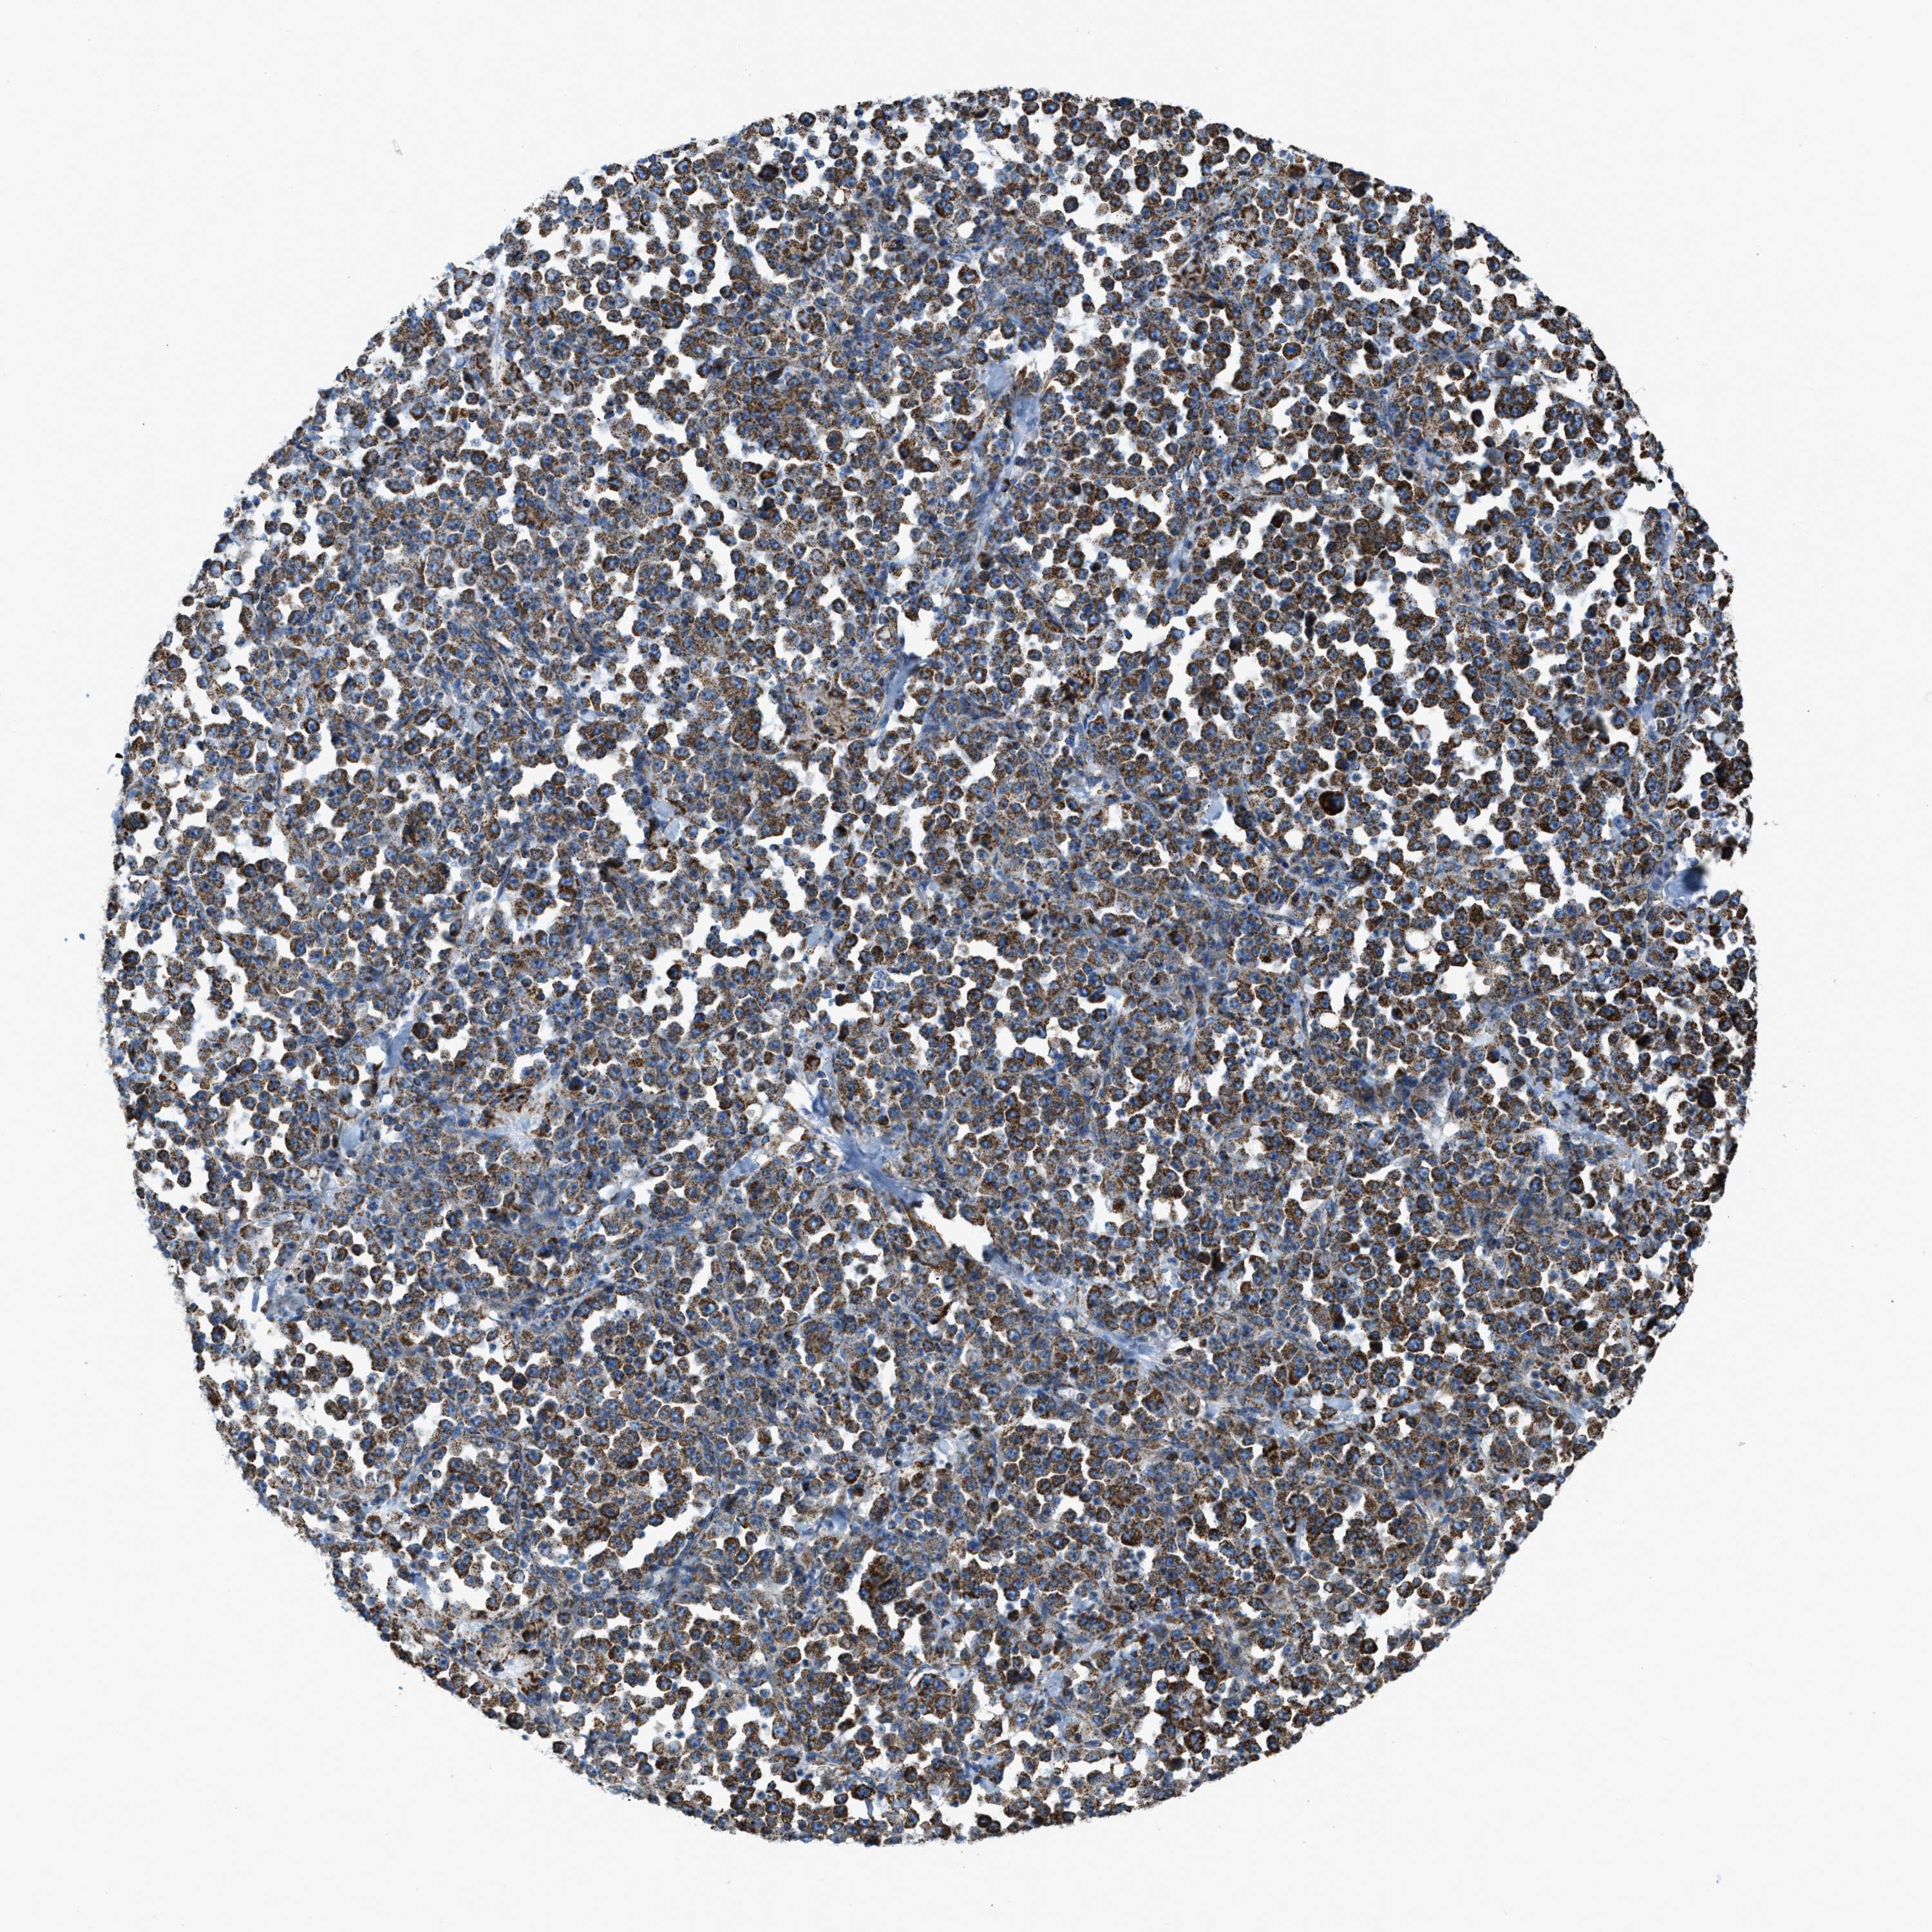

STOMACH CANCER - Protein expressioni

A mouse-over function shows sample information and annotation data. Click on an image to view it in a full screen mode. Samples can be filtered based on level of antibody staining by selecting one or several of the following categories: high, medium, low and not detected. The assay and annotation is described here.

Note that samples used for immunohistochemistry by the Human Protein Atlas do not correspond to samples in the TCGA dataset.

Antibody stainingi

Antibody staining in the annotated cell types in the current human tissue is reported as not detected, low, medium, or high, based on conventional immunohistochemistry profiling in selected tissues. This score is based on the combination of the staining intensity and fraction of stained cells.

Each image is clickable and will lead to virtual microscopy that enables deeper exploration of all samples and also displays staining intensity scores, fraction scores and subcellular localization as well as patient and tissue information for each sample.

Antibody HPA018910

Antibody HPA018921

Antibody HPA018923

Staining

High

Medium

Low

Not detected

Intensity

Strong

Moderate

Weak

Negative

Quantity

>75%

75%-25%

<25%

None

Location

Nuclear

Cytoplasmic/membranous

Cytoplasmic/membranous,nuclear

Adenocarcinoma, NOS